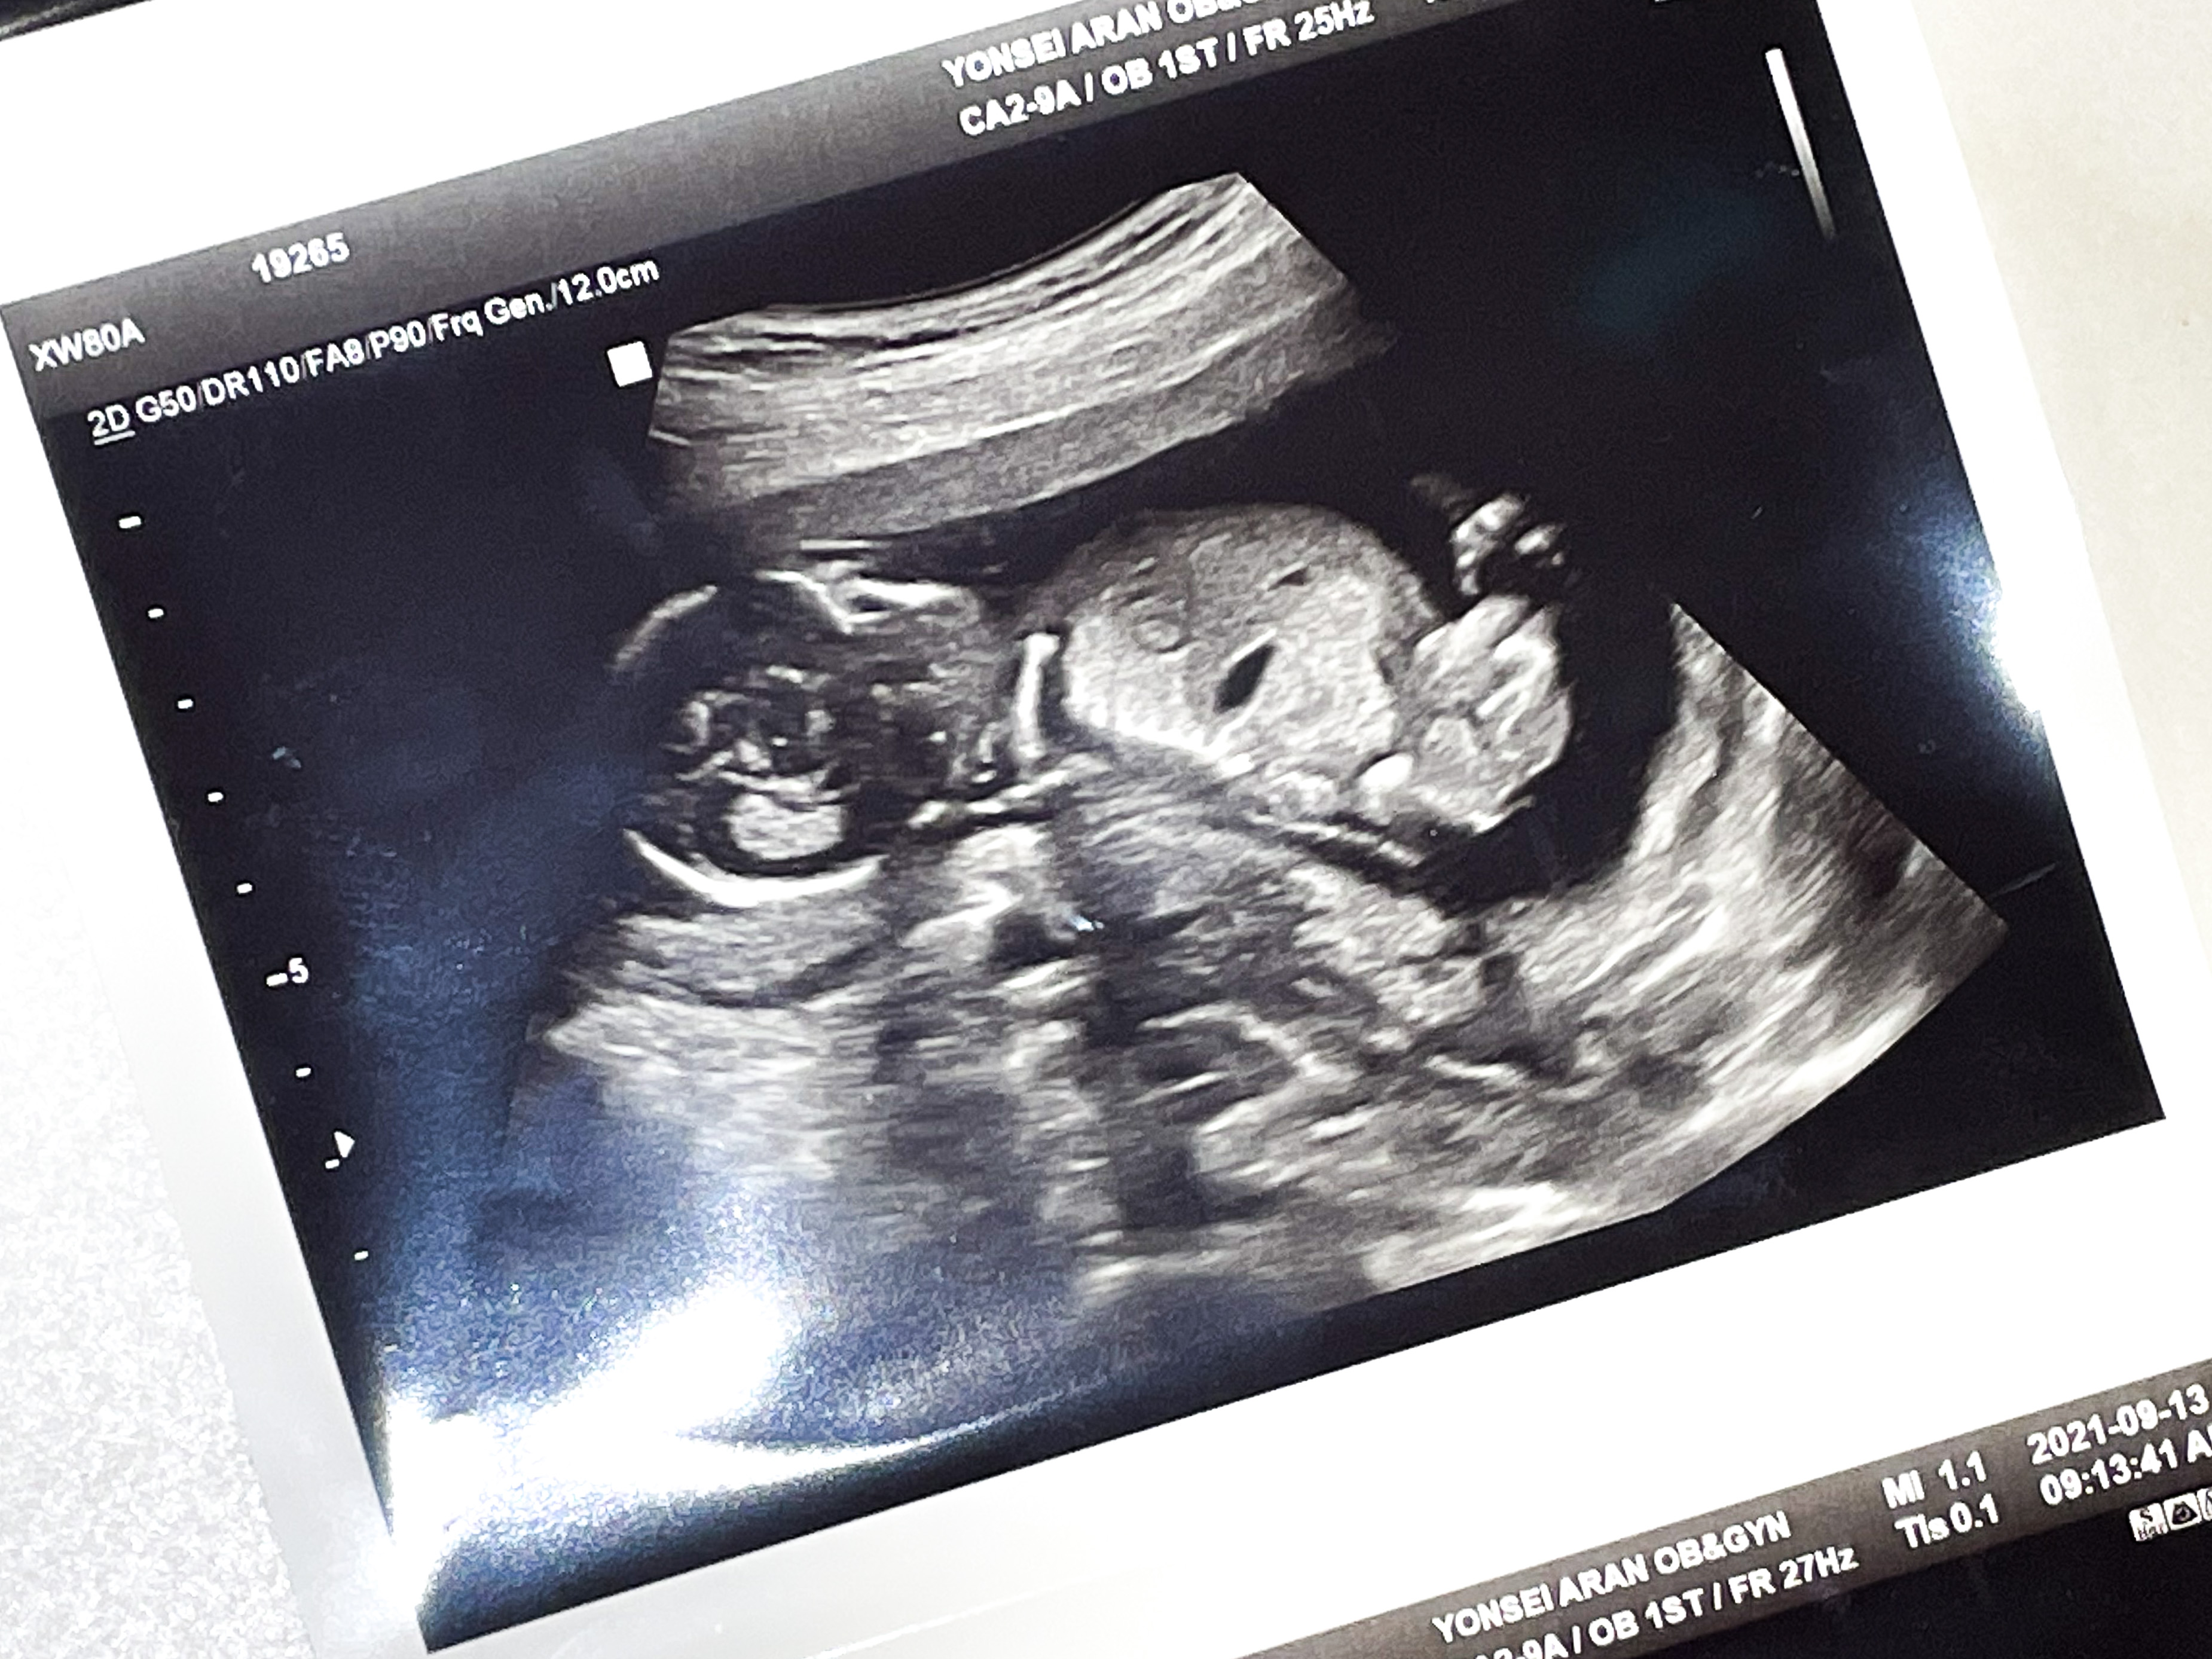

15주 4일 2차 기형아 검사를 받으러 갔다.

먼저 담당 원장님과 초음파를 확인했다.

벌써 애가 많이 커서 한 프레임 안에 담기지가 않았다.

애기가 한프레임 안에 안담기다보니 앉은키를 잴 수 없다고 했다.

대신 정강이뼈 길이, 몸무게 등등을 측정해주셨다.

체중(EFW): 132g

머리직경(BPD): 3.26 cm

머리둘레(HD): 12.35 cm

복부둘레(AC): 10.68 cm

허벅지길이(FL): 1.57 cm